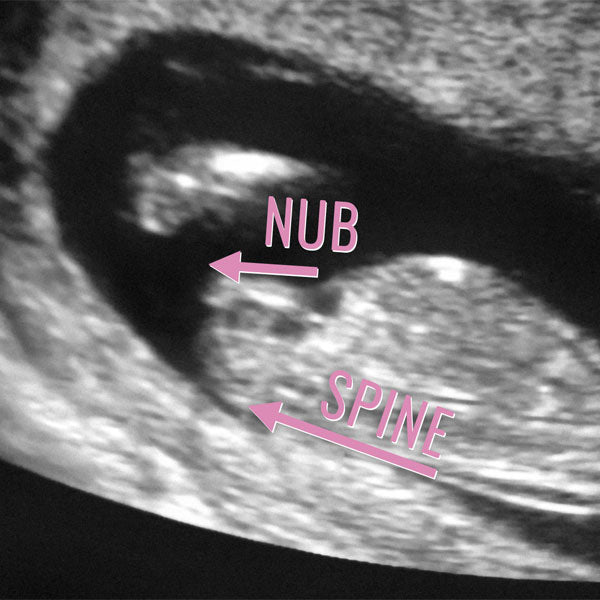

NUB THEORY

To determine gender, The Gender Experts use the following criteria:

- Visibility

- The angle of genital tubercle in relation to the spine

- Shadows and male markers on and surrounding tip of nub

- Shape, including length according to gestational age